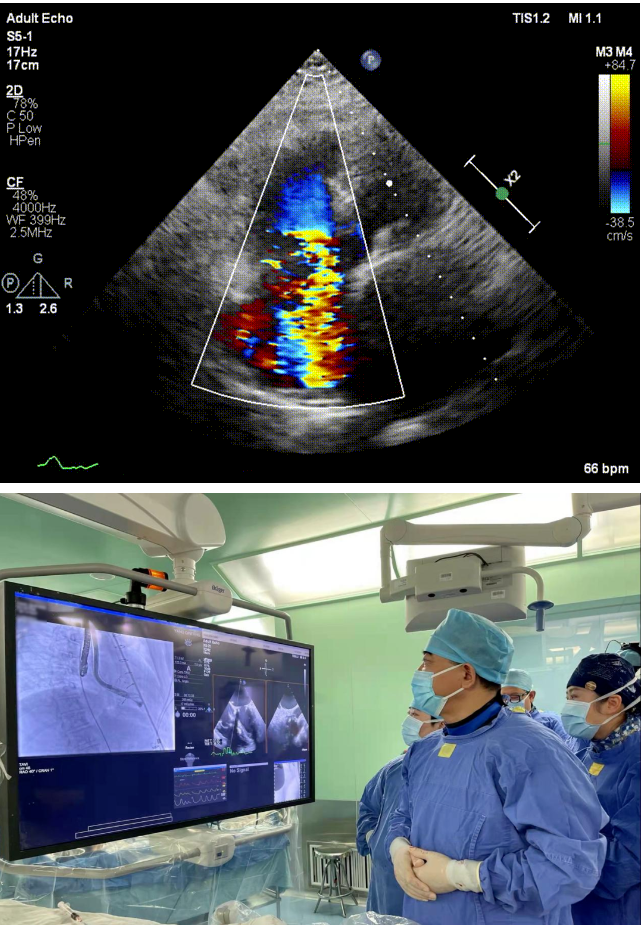

本次接受治療的患者是一名74歲的女性,14年前因風濕性心臟病行二尖瓣生物瓣植入術,合并房顫。近3年來反復因腹脹、納差、下肢水腫入院,藥物治療欠佳。心臟超聲顯示三尖瓣極重度反流(有效反流口面積:0.76cm²,反流容積:79ml),繼發性右房室增大及上、下腔靜脈增寬(右房上下徑*左右徑:52*41mm,右室左右徑:46mm,下腔靜脈:29mm),右室收縮功能正常,肺動脈收縮壓 43mmHg,左心室射血分數73% ?;颊呒韧_胸手術史,術前評估STS 評分為7.02分,CRS 9分,無法接受體外循環下三尖瓣外科手術。面對這一傳統治療無法解決的困境,葛均波院士及其團隊周達新教授、潘文志教授、張源博士、陳莎莎博士及心超室的潘翠珍教授、李偉教授經過討論決定,采用創新的Lux-Valve Plus系統為患者進行經血管三尖瓣置換。

手術在患者全麻狀態下進行,采用經右側頸靜脈作為入路,將裝載有人工瓣膜的輸送器緩慢推送至右心房;并在經食道超聲和DSA的引導下小心調整輸送器角度,將輸送器送入右心室;逐步釋放瓣膜錨定裝置和盤片,調整瓣膜位置后,錨定瓣膜完成植入。術后右房壓明顯下降,從術前的25/10(16) mmHg降至術后即刻的12/7(10) mmHg,術后超聲提示人工三尖瓣同軸性良好,固定牢固,無反流及瓣周漏,手術室即刻拔除氣管插管。